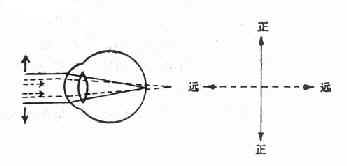

1.单纯性散光:一条主经线为正视,另一条主经线为远视(单纯远视散光)或近视(单纯近视散光)。

图16-10 单纯远视散光